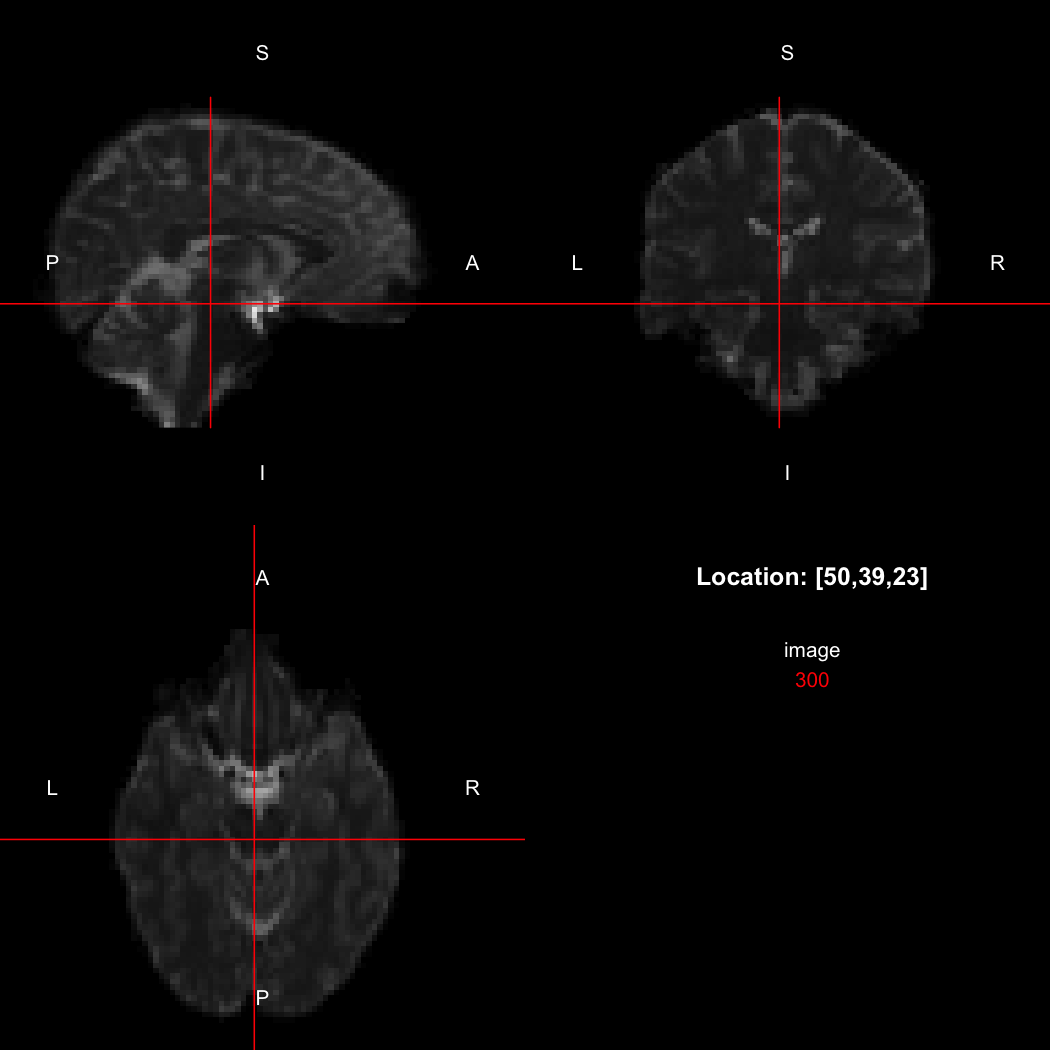

The package contains a basic image viewer, which can be used interactively or noninteractively to examine 2D or 3D images.

view(image)

plot of chunk unnamed-chunk-5

By default, the viewer shows labels indicating image orientation, crosshairs pinpointing the currently selected location, the numerical indices of the current location, and the value of the image at that location. Options allow each of these to be turned off, for the content of the bottom-right panel to be customised entirely, for the colour scale to be changed, and for additional images to be layered on top of the base image. See ?view for details.

So, here, “LAS” means that the positive x-axis points left, the positive y-axis anterior and the positive z-axis superior. This is the so-called “radiological” orientation convention, and can be requested when viewing images for those who are used to it:

view(image, radiological=TRUE)

plot of chunk unnamed-chunk-12

Notice the left (L) and right (R) labels, relative to the view shown above. Setting the radiologicalView option to TRUE will make this the default for all future views.

image[50,39,23]

## [1] 300